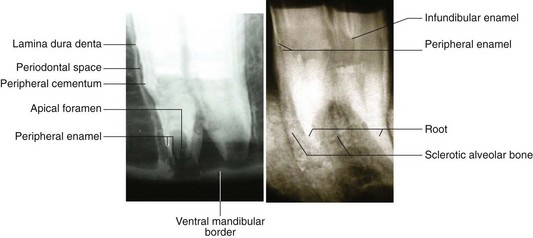

80 Dixon PM, Gerard M. Oral cavity and salivary glands. In: Auer G, Stick JA. Equine surgery. 3rd edn. St Louis: Elsevier; 2008:321–350.